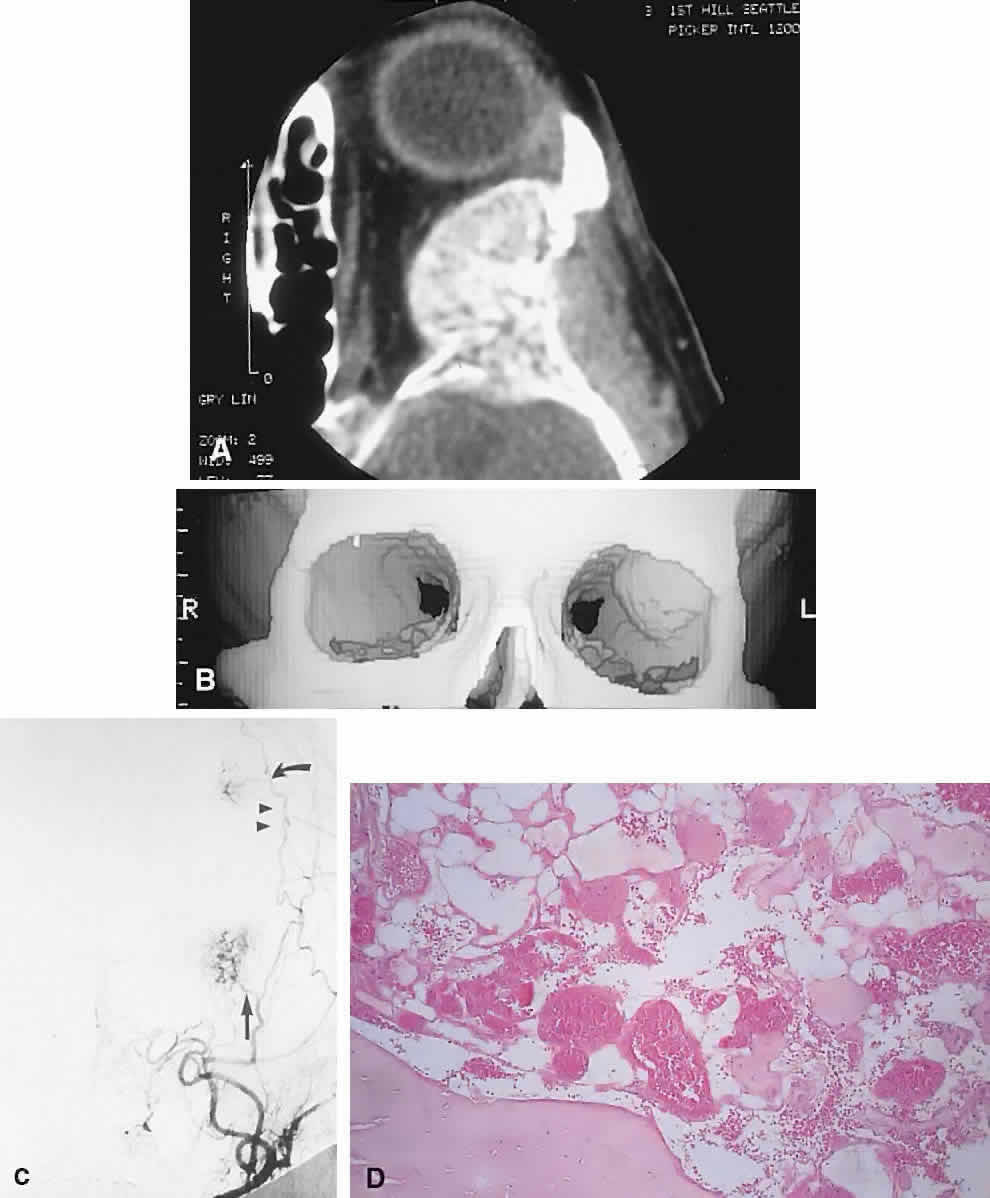

IMAGING. Intraosseous hemangiomas present as well-defined, radiolucent masses that expand the inner and outer tables of the bone, often in an asymmetric fashion. Approximately half show the classic picture of a sunburst, striated, or honeycombed internal pattern (Fig. 13). On selective angiography, they appear as a tangle of vessels.155

Fig. 13. A 65-year-old woman with slowly progressive left proptosis. A. CT showed a well-defined, expansile lesion of the greater wing of the sphenoid, which demonstrated a spiculated internal pattern. B. A 3D CT illustrated the expansion of the bone of the lateral orbital wall. C. Subtraction angiography revealed a tangle of vessels at the site of the orbital mass (arrow) in addition to a smaller, more superior lesion in the frontal bone (curved arrow). After preoperative embolization, the mass was excised with a rim of normal bone. D. Histology showed an intraosseous hemangioma with large cavernous, endothelial-lined, blood-filled spaces (hematoxylin-eosin, × 20). (C from Rootman J, Kao SCS, Graeb DA: Multidisciplinary approaches to complicated vascular lesions of the orbit. Ophthalmology 9:1440–1446, 1992.)

HISTOPATHOLOGY. The specimen consists of soft, violaceous masses with intervening trabeculae of reactive bone. Microscopically, most are cavernous hemangiomas with large endothelial-lined, blood-filled vascular spaces.156

MANAGEMENT. Surgical treatment consists of excision with a rim of normal bone. Preoperative angiography should be performed and strong consideration given to embolization before resection, because these tumors can bleed in a profuse and persistent manner.155